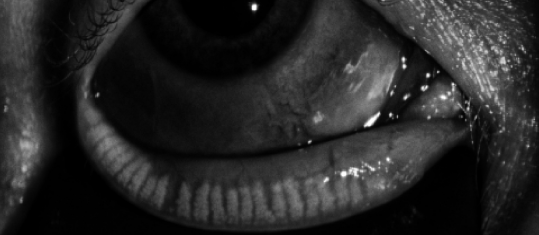

This is a patient who gave me permission to post her meibography of her right lower lid before and after Lipiflow. She was having significant foreign body sensation and irritation.

This is 9/9/16 Right Lower Lid

This 11/2/17 Right Lower Lid

The same technician did the study. You can see the improvement clearly.